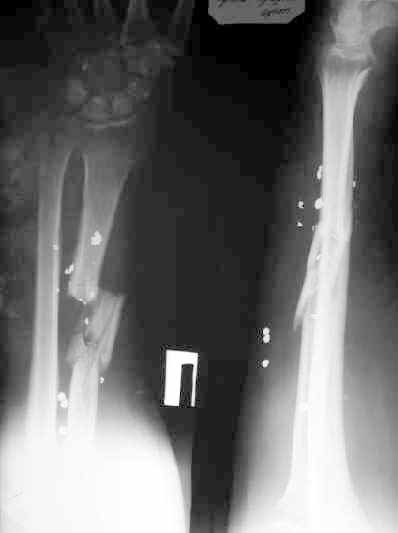

A male 36 years old 5 month ago sustained a gun-shot wound with the radial fracture and lesion of a. radialis and n. medianus. Debridement was performed at the initial hospital, full-thickness skin grafting and intramedullary fixation of the radius by a small wire, which later was removed. No sinuses and signs of infection to date. A linear scar on the radial side and the healed flap (see image). Healing was not reached (see x-rays).

This patient has a radius shaft segmental fracture with nonunion, healed soft tissue with scar, nerve and probably tendon injuries but a well perfused hand, probably not infected and an intact ulna.

By a quite invasive open mobilization and reduction... So it seems reasonable to restore length and axis gradually. A distractor was applied, an, the x-ray is performed after strong manual traction.